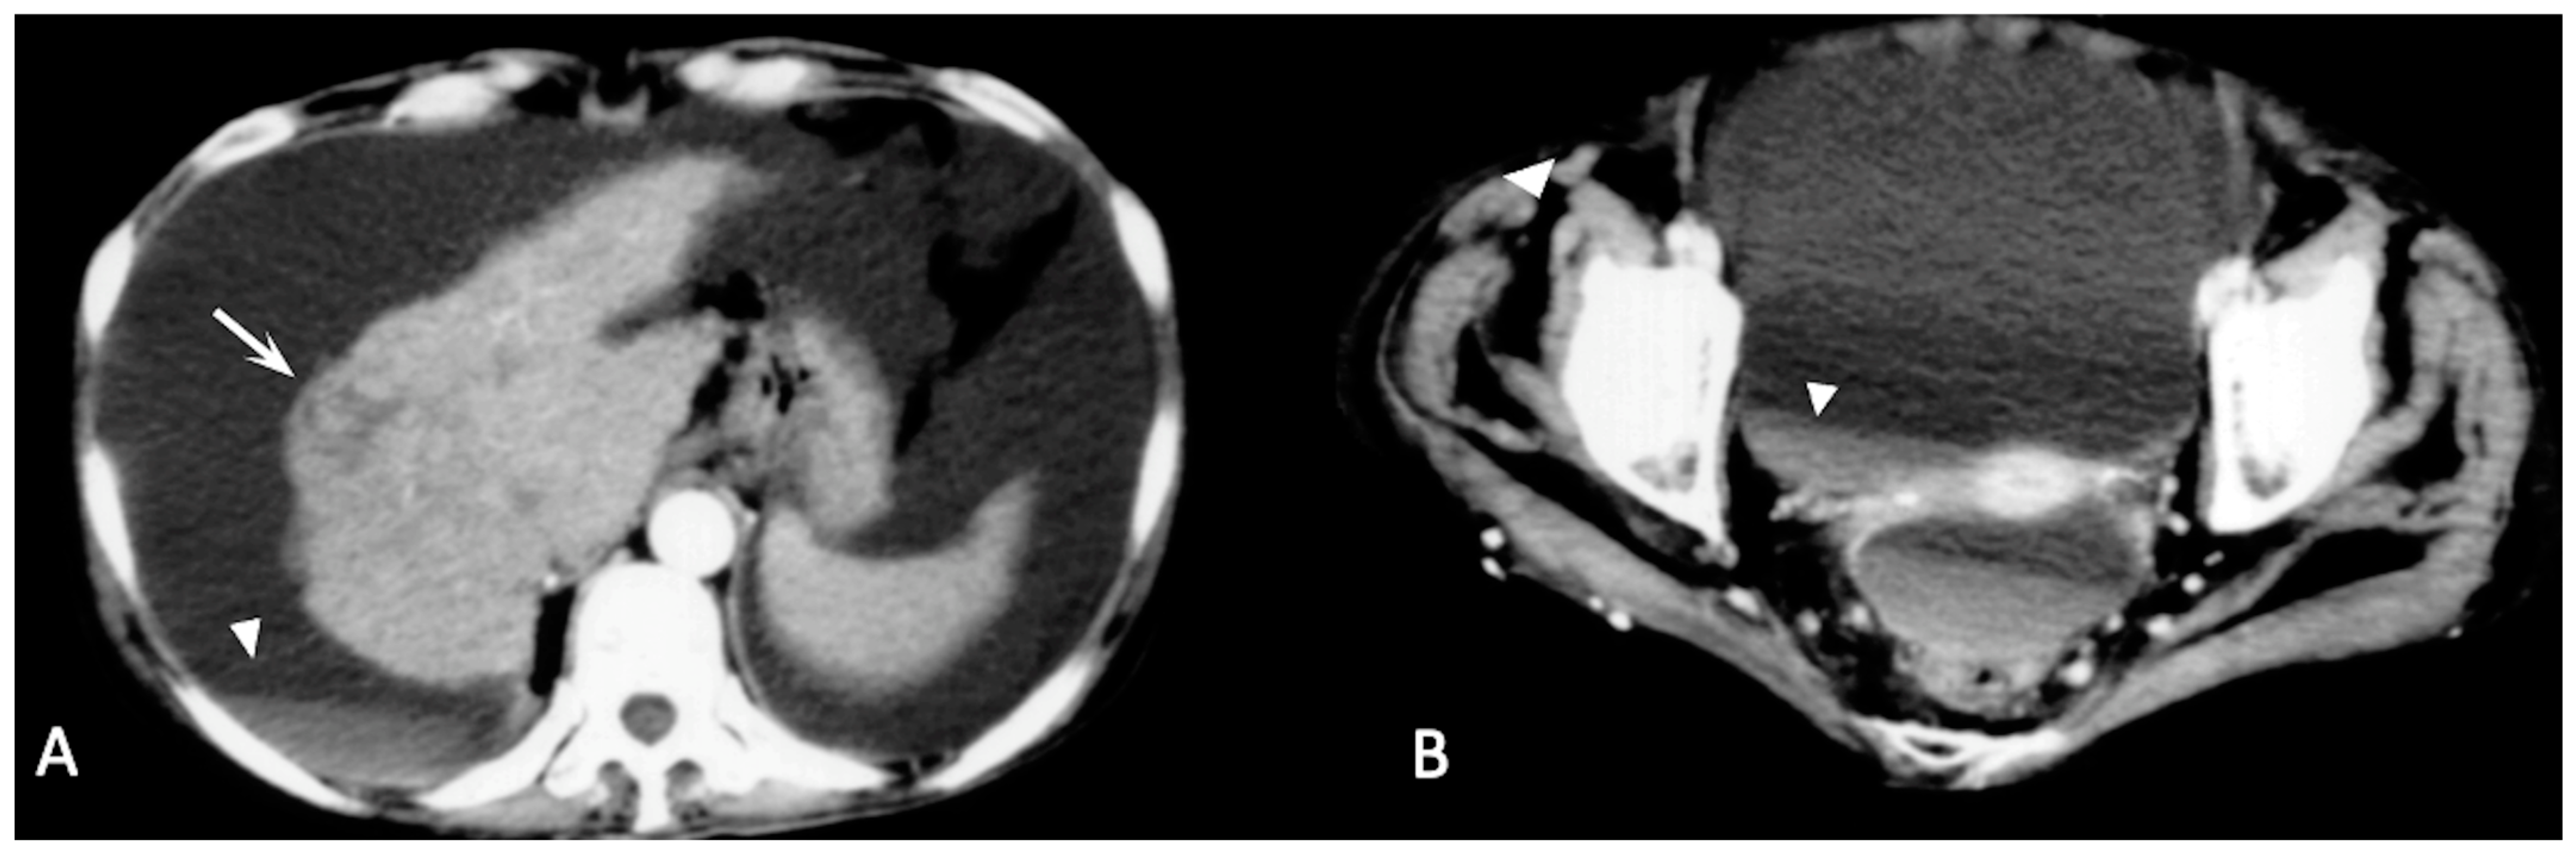

2. CT Findings

2.2. Spontaneously Ruptured HCC (SRHCC)